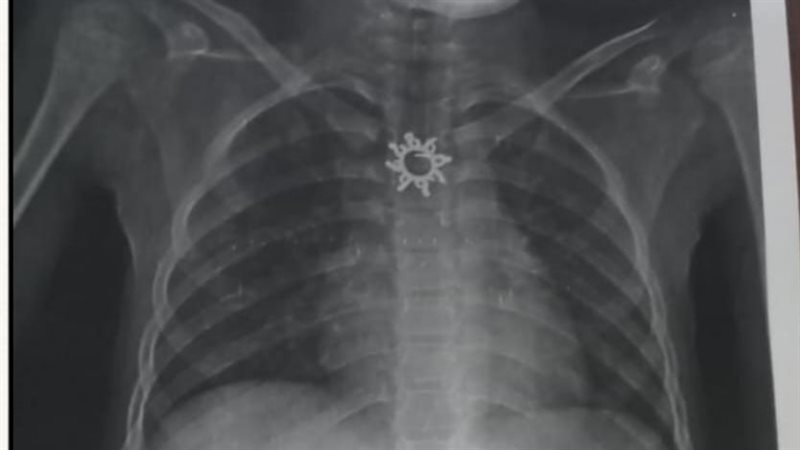

أستخرج سلسلة معدنية مدببة الأطراف ابتلعتها طفلة عمرها 9 سنوات بأبو كبير

وأوضح الدكتور أحمد البيلي وكيل وزارة الصحة أن قسم المناظير بمستشفى أبو كبير شهد نجاح مميز في إنقاذ الطفلة التي تبلغ من العمر ٥ سنوات، وقامت بابتلاع سلسلة معدنية حادة ومدببة وأطرافها قادرة على إحداث جروح أو ثقوب بالزور أو داخل المعدة، وبعد استقبالها مساء أمس الثلاثاء بمستشفى مشتول السوق المركزي، وتم التنسيق السريع من خلال مركز الخدمات الطارئة ١٣٧ بالمديرية، وتحويل الحالة بسيارة الإسعاف إلى مستشفى أبو كبير في وقت قياسي، وتم التدخل العاجل بالمنظار بعد إجراء كافة الفحوصات الطبية اللازمة لها، واستخراج السلسلة من المعدة دون أي مضاعفات، وسط متابعة وتدخل فوري من الفريق الطبي بقيادة الدكتور محمد عصام خلال الفترة المسائية.